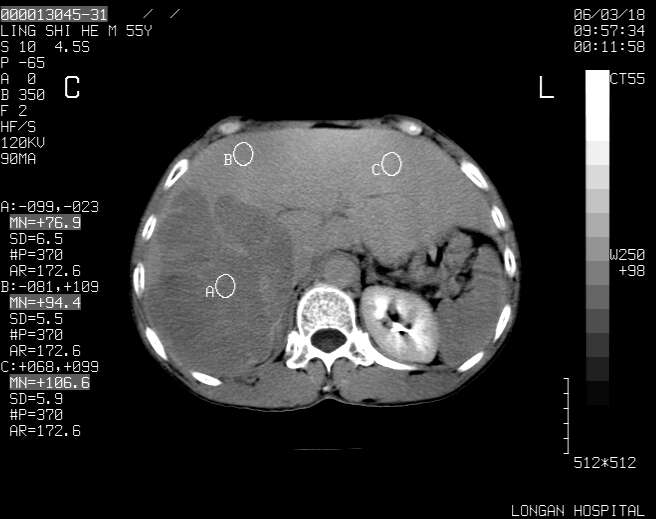

以下是引用guzhongliangddd在2006-3-21 22:13:00的发言:[br]病灶主要位于肝右叶的后份,内见异常血管,门脉主干及右支受侵{提示有癌栓形成},门腔间隙内见增大淋巴结。肝左叶内未见异常。

以下是引用zhuxinli在2006-3-22 1:23:00的发言:[br][br] 病灶主要位于肝右叶的后份,内见异常血管 .门脉右支截断,右叶前段早期强化(考虑动静脉漏),腹膜后肿大淋巴结,病灶逐渐强化,考虑为胆管细胞癌[br]